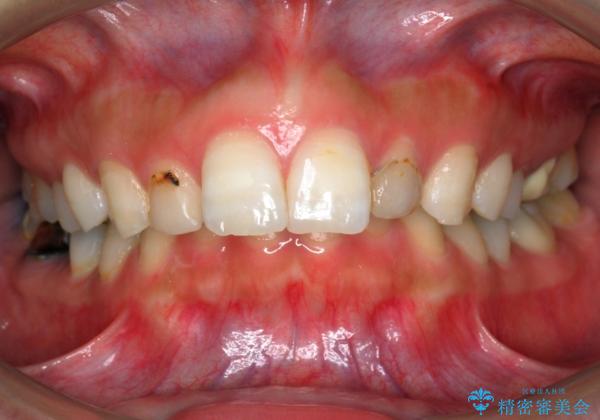

出っ歯を治したい 過蓋咬合

- 出っ歯を主訴に来院。

かみ合わせが深く、治療に時間がかかりました。

上顎2番は矮小歯だったのをセラミックで被せています。

口唇の突出感がなくなり、理想的な横顔になりました。

虫歯治療は、他院で保険治療で行なって頂いています。